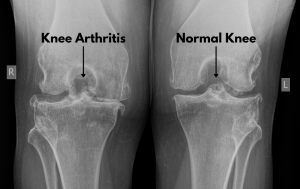

Most knee arthritis diagnoses begin with a simple X-ray. This imaging test shows joint space narrowing, bone spurs, and structural changes that confirm osteoarthritis. While an X-ray is a start, your doctor may order an MRI to evaluate cartilage loss or soft tissue damage if your symptoms are more complex.

X-rays use electromagnetic energy to capture real-time images of bones. This process is usually done by a radiologist, who will interpret the images to confirm a diagnosis. X-rays are commonly used to diagnose broken bones, arthritis, and foreign objects in the body.

When radiologists are diagnosing knee arthritis, they will typically look for joint space narrowing, which indicates that there’s a loss of cartilage. They will also look for bone spurs, which occurs when the erosion of cartilage leads to friction between the bones and encourages new bone growth to keep the joint steady. Both signs can trigger inflammation in the blood vessels surrounding the joint, which contributes to knee pain and swelling.

X-rays are typically the first imaging test used to evaluate knee arthritis because they clearly show changes in bone structure, joint space narrowing, and the presence of bone spurs. These findings help confirm osteoarthritis and assess its severity.

X-rays are excellent for visualizing bone structures; however, because cartilage does not absorb electromagnetic energy, they are unable to show the soft tissue, which is the first part of the knee affected by arthritis. This limitation makes it difficult to diagnose early-stage knee arthritis with X-rays alone. Therefore, specialists frequently turn to advanced imaging to get a complete picture. For example, an MRI can visualize cartilage, ligaments, and other soft tissues, which are essential for detecting knee arthritis at an earlier stage.